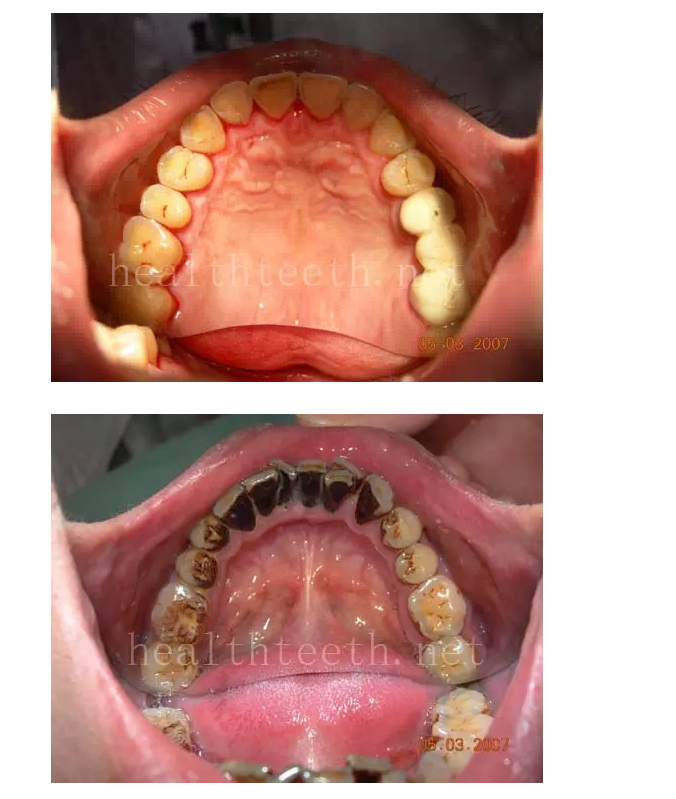

18歲孩子的口腔狀況

30歲人的口腔狀況